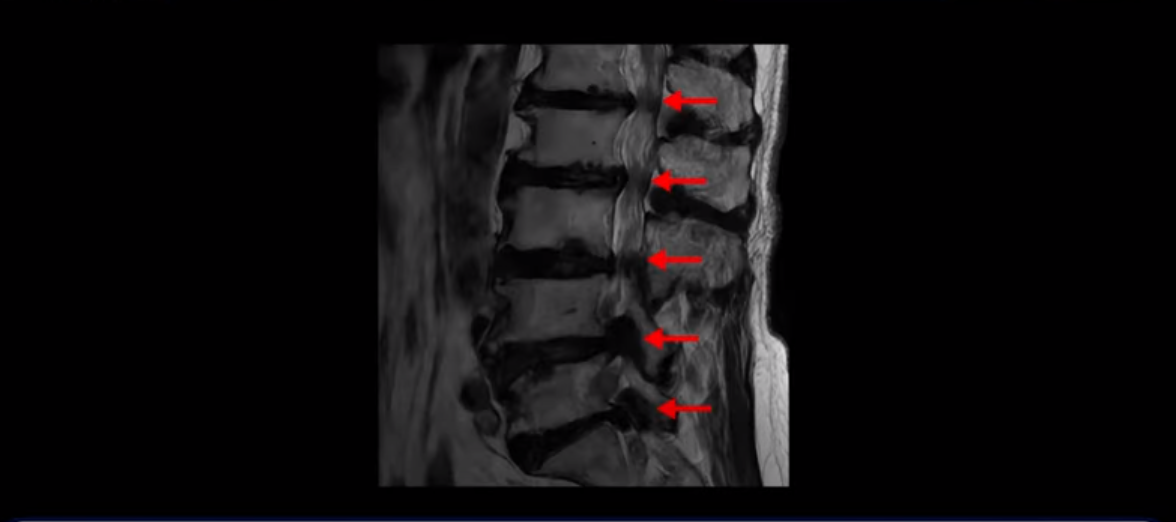

이 환자분은 MRI로 보면 허리 여러 마디가 신경이 매우 심하게 눌려 보이는 분입니다. 이분 MRI를 보면서 간단히 설명해 드린 후 어떻게 이렇게 신경이 심하게 눌린 환자분이 수술 없이 근육신경재활치료로 좋아질 수 있는지, 다리가 아파 걷지 못하는 환자가 어떻게 안 아프고 잘 걸을 수 있게 되는지, 10년 동안 괴로웠던 양 발의 시린 증상은 어떻게 사라질 수 있는지, 치료는 어떻게 하는지 자세히 설명 드리겠습니다.

MRI 보시면 (2-8) 허리의 5마디가 전부 다 심하게 퇴행되어 있습니다.

5마디 전부 다 심한 중심성 협착이 있습니다.

1번 2번,

2번 3번,

3번 4번,

4번 5번,

5번 6번

이렇게 모두 다 심하게 막히는 경우는 드문데요. 또한 오른쪽, 왼쪽 신경이 빠져나가는 추간공도 다 심하게 막혀있습니다.

오른쪽, 왼쪽 이렇게 신경 구멍들이 다 좁아지고 신경이 눌리니까 양쪽 다리가 발바닥까지 아파서 걷기 어렵고 양쪽 발이 10년 넘게 시린 겁니다. 당연히 수술해서 눌린 신경을 풀어줘야 한다고 들으셨는데요. 이런 환자분을 어떻게 수술 없이 치료할까요? 지금부터 설명해 드립니다.